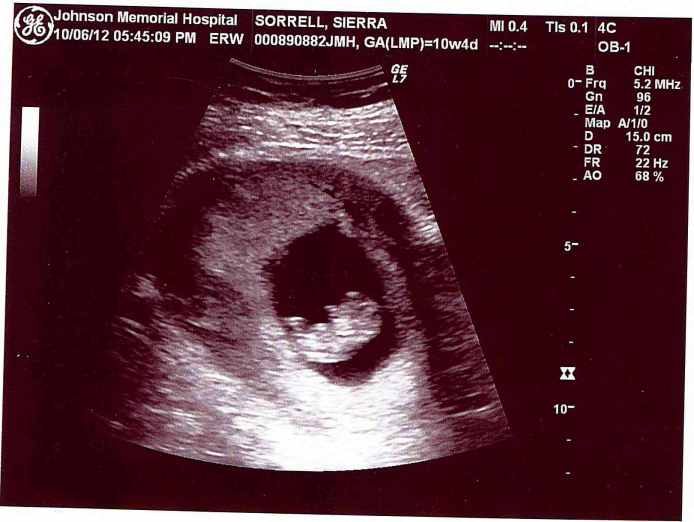

So let me catch you up on what you’ve missed over the past 35-or-so days…. We had our first ultrasound on 10/6; The baby looked like a shrimp and since has been dubbed with the nickname Scampi. And we shared our news with a small handful of people. My sister cried. Frankie said, “God is good!” Chris’ mom’s eyes crinkled with the biggest smile I’ve ever seen on her face. Chris’ dad held my hand across the breakfast table while we waited for the waitress to deliver food. My sister’s boys asked if it was planned (yes, DeShawn) and if they could choose the baby’s name (no, Anthony). I’m told that Chris’ twin brother Dave said, “Dude, this is a pretty big deal.” Our closest friends cheered and congratulated Chris on “getting the job done!” But the best reaction of them all was my dad’s.

After leaving the ultrasound appointment, I texted my father to ask if I could stop by to talk to him. And within about 30 minutes I found myself in the living room of the home I grew up in. I asked him to put on his glasses and turn on a light, which he did. I then handed him the ultrasound photo. He stared at it, smiled, and asked, “Uh…where is this?” I got teary so my sister lightened the mood. “Well, it’s not in Chris!” He teared up and said, “This is wonderful news, doll. Seeing you have kids is one of the things I still had to accomplish in my life and I’m so happy for you.” (Unbeknownst to me until that night, my father had been asking my sister for a year or so if she thought I’d ever start a family. And knowing my fears about conceiving, she has been telling him not to pressure me.)